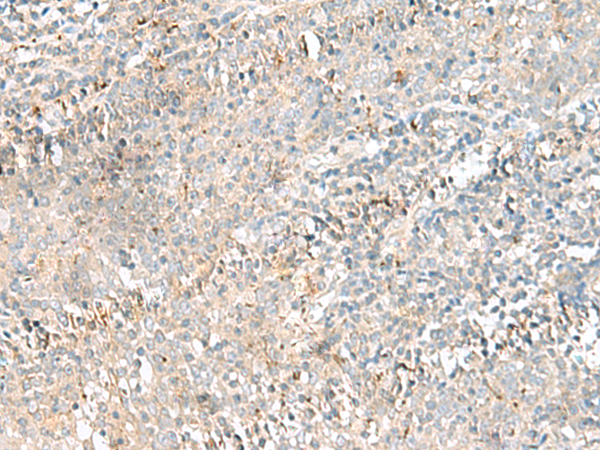

分类: 科研抗体货号: P09851别名: TTF; ARHH应用: IHC反应种属: Human, Mouse

分类: 科研抗体货号: P09870别名: BCM1; BLAST; hCD48; mCD48; BLAST1; SLAMF2; MEM-102应用: WB,IHC反应种属: Human

分类: 科研抗体货号: P09881别名: CTRB应用: WB,IHC反应种属: Human, Mouse, Rat